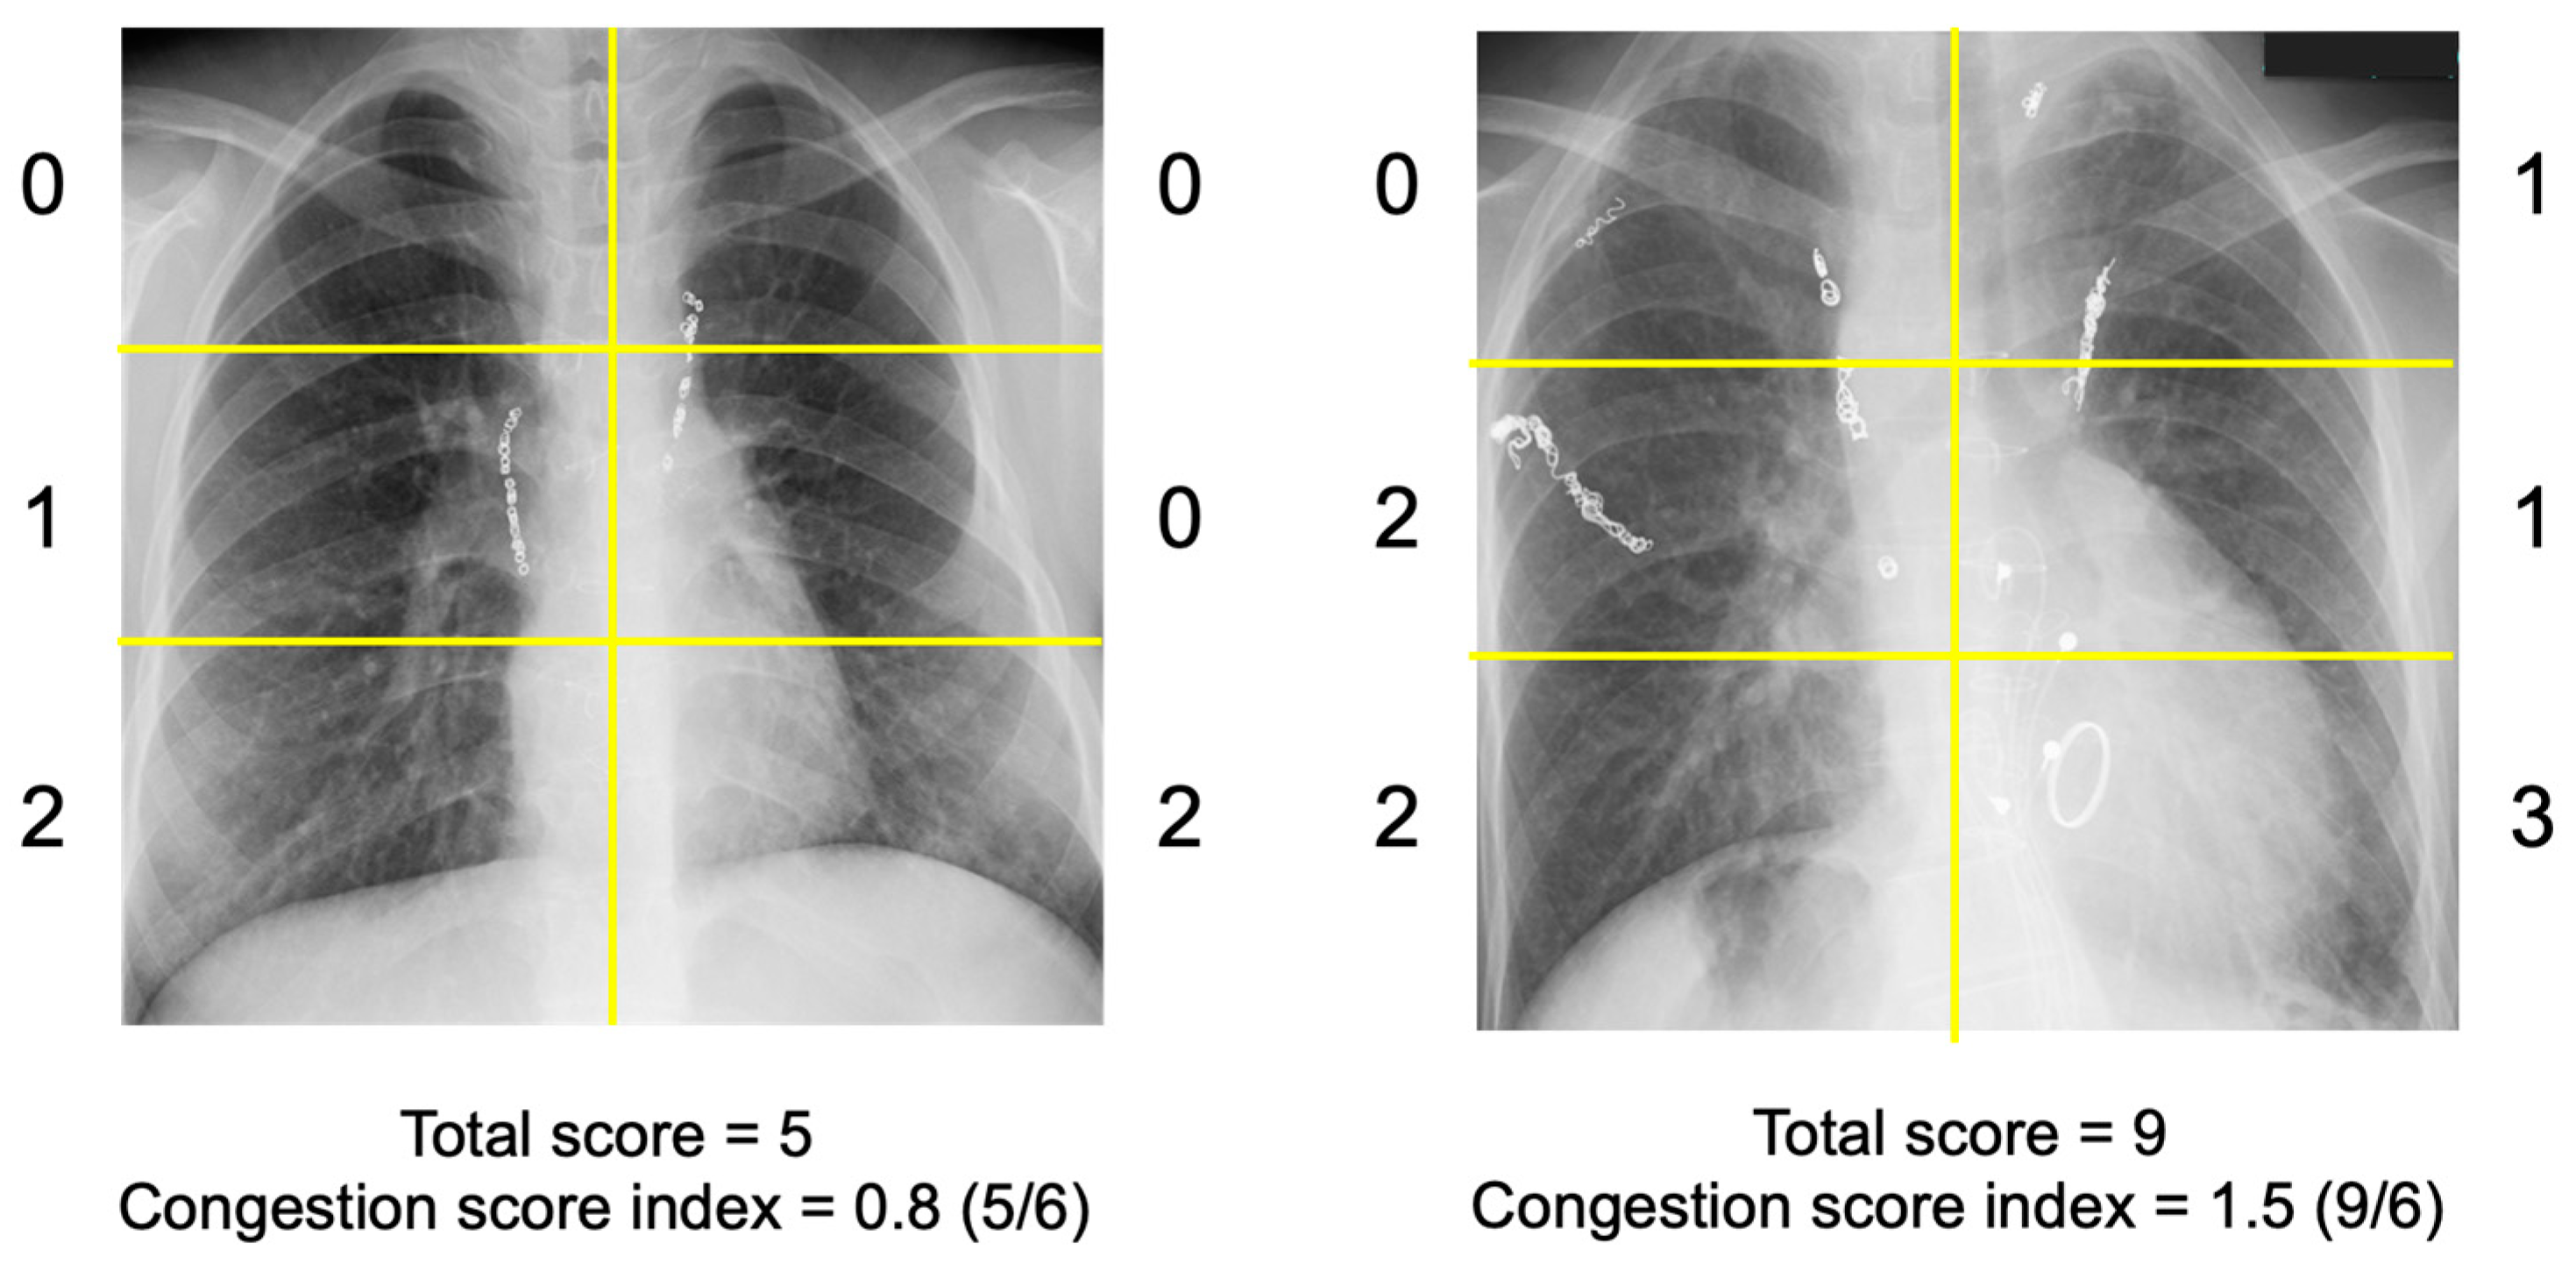

2.3. Measurement of Congestion Score Index from Chest X-Ray

| Congestion score index | 0.83 (0.64, 1.08) |